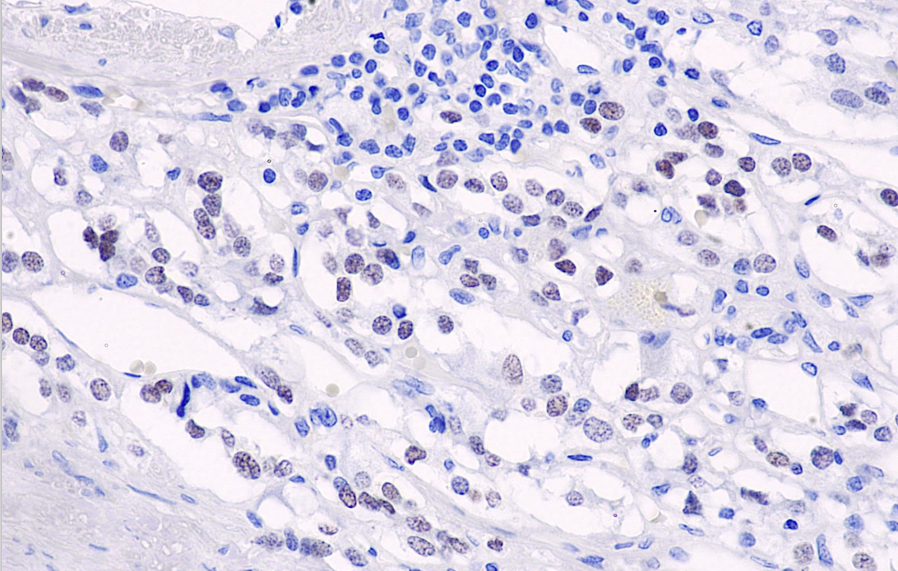

Cellular localization: nucleus

Positive control: chromophobe tumor

The PHOX2B (Paired-like homeobox 2B) gene is located on chromosome 4p13 and functions as a nuclear transcription factor, primarily promoting the differentiation of autonomic neurons during embryonic development. Peripheral PHOX2B is highly expressed in both differentiated and undifferentiated peripheral neuroblastoma (including neuroblastoma, paraganglioma, ganglioneuroblastoma, ganglioneuroma/astrocytoma) and pheochromocytoma. It is not expressed in other types of small round blue cell tumors (such as Wilms' tumor). It can serve as a diagnostic marker for neuroblastoma. Research has also shown that mutations in this gene are associated with congenital megacolon.

PHOX2B antibody reagents can specifically bind to PHOX2B molecular antigens. Immunohistochemistry kits containing PHOX2B antibody reagents are suitable for the precise diagnosis of neuroblastoma.